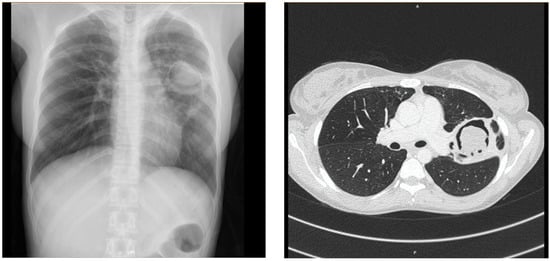

| Cavity | 22 (22%) | 61 (82.4%) | <0.001 |